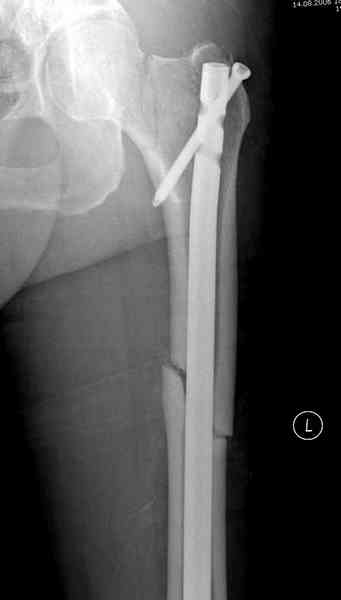

В первый же день произведено антеградное штифтованием DePuy Trochanteric Nail.

и проведены шурурпы через и спереди штифта без удаления.

Послеоперационные снимки